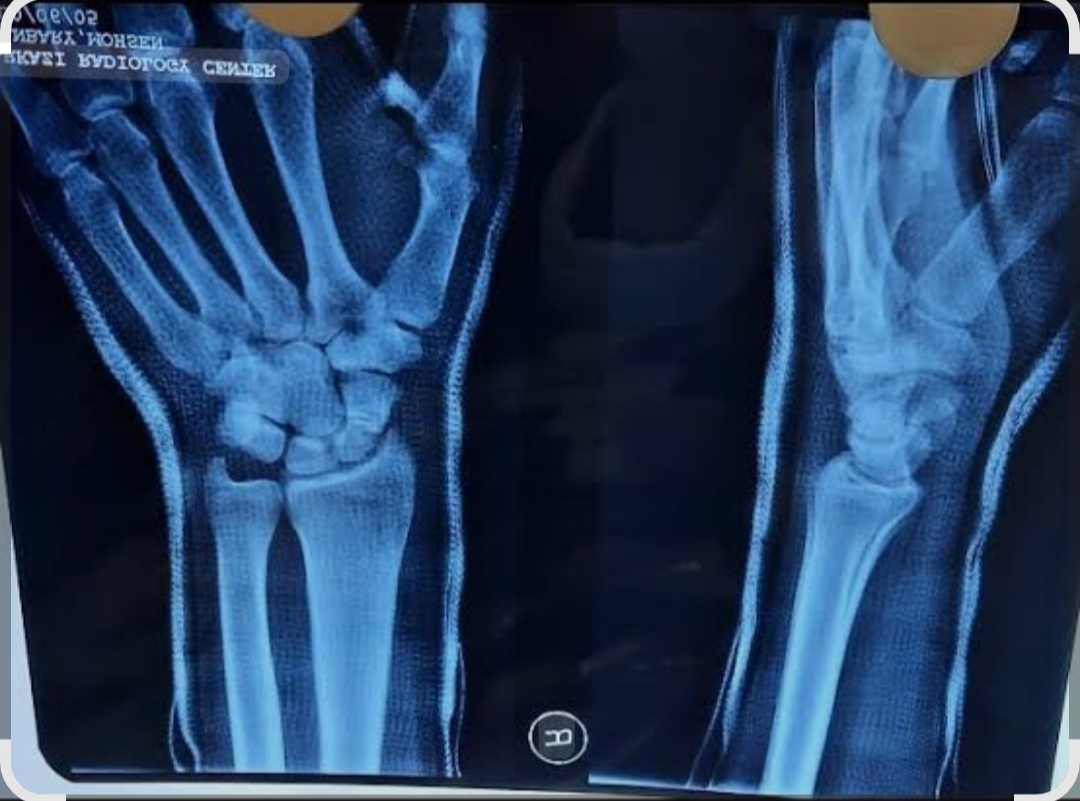

- درمان شکستگی ها و دررفتگی های اندام فوقانی و تحتانی